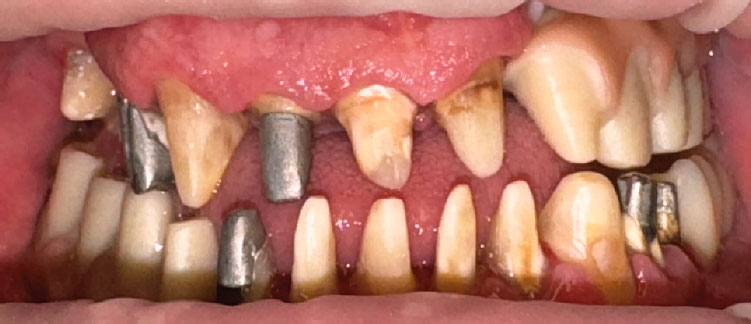

Пациент Б., 57 лет, обратился с жалобами на нарушение жевания из-за отсутствия зубов и на неудобное положение нижней челюсти. Из анамнеза: 9 лет назад пациенту на верхней и нижней челюстях были установлены дентальные имплантаты «Nobel» (Nobel Biocare, Швейцария), которые со временем дезинтегрировались (рис. 1, 2).

Рис. 2. Зубные ряды пациента в вынужденном положении нижней челюсти

Fig. 2. Patient’s teeth with a forced position of the mandible